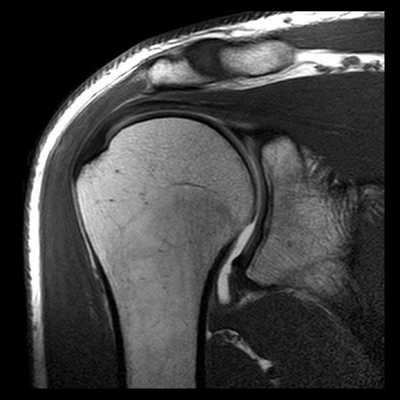

У каждого способа обследования имеются свои преимущества и недостатки. На сегодняшний день ведущую роль в визуализации вне- и внутрисуставных структур плечевого сустава играет МРТ, которая позволяет выявлять мягкотканные и костные повреждения в суставах. Она может осуществляться по двум базовым протоколам - бесконтрастная томография и МРТ плечевого сустава с применением парамагнитных контрастных веществ (она же МР артрография). Лидирующую роль в оценке состояния костей плеча играет спиральная компьютерная томография.

МР-оценка повреждений суставной губы и связок плечевого сустава при артрографии совершенствуется. Для оценки повреждений ротаторной манжеты плеча артрография, как правило, не требуется. Некоторые рентгенологи утверждают, что она может быть полезной при описании малых разрывов на половину толщины структуры. Данные о том, что такое описание влияет на хирургическую тактику пока не получены.